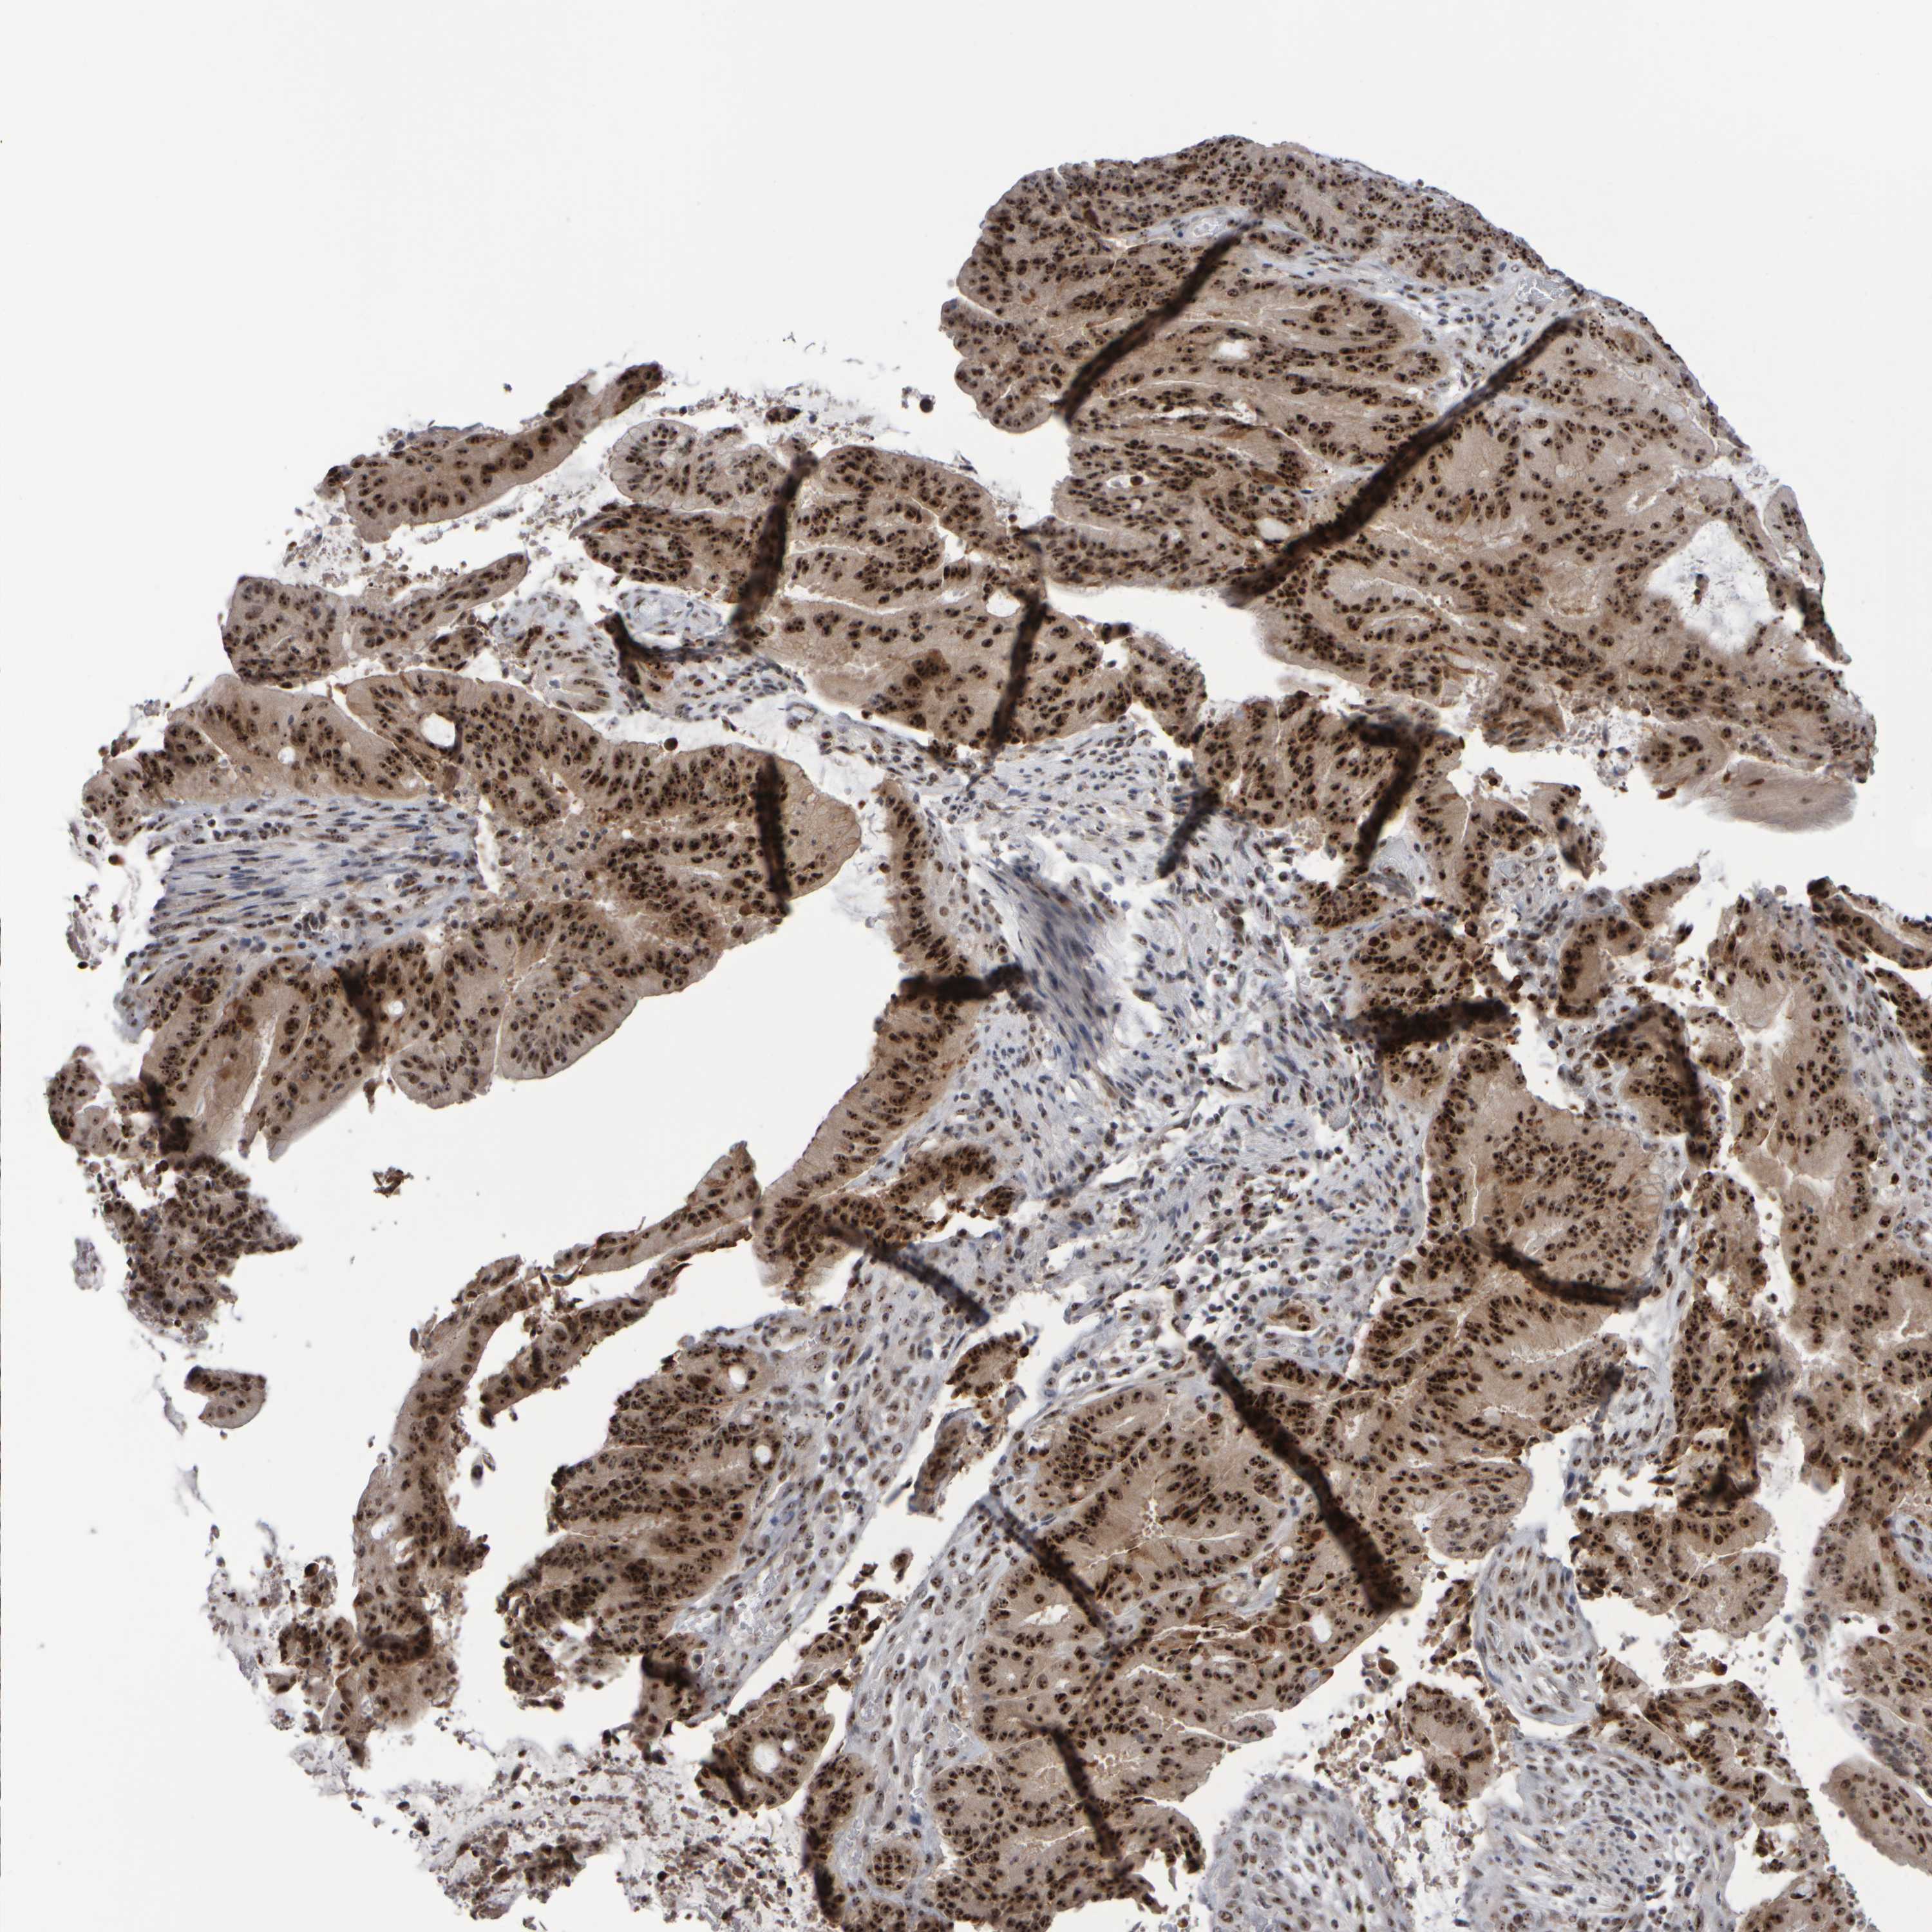

LIVER CANCER - Protein expressioni

A mouse-over function shows sample information and annotation data. Click on an image to view it in a full screen mode. Samples can be filtered based on level of antibody staining by selecting one or several of the following categories: high, medium, low and not detected. The assay and annotation is described here.

Note that samples used for immunohistochemistry by the Human Protein Atlas do not correspond to samples in the TCGA dataset.

Antibody stainingi

Antibody staining in the annotated cell types in the current human tissue is reported as not detected, low, medium, or high, based on conventional immunohistochemistry profiling in selected tissues. This score is based on the combination of the staining intensity and fraction of stained cells.

Each image is clickable and will lead to virtual microscopy that enables deeper exploration of all samples and also displays staining intensity scores, fraction scores and subcellular localization as well as patient and tissue information for each sample.

Antibody HPA023608

Staining

High

Medium

Low

Not detected

Intensity

Strong

Moderate

Weak

Negative

Quantity

>75%

75%-25%

<25%

None

Location

Nuclear

Cytoplasmic/membranous

Cytoplasmic/membranous,nuclear

Cholangiocarcinoma

Carcinoma, Hepatocellular, NOS